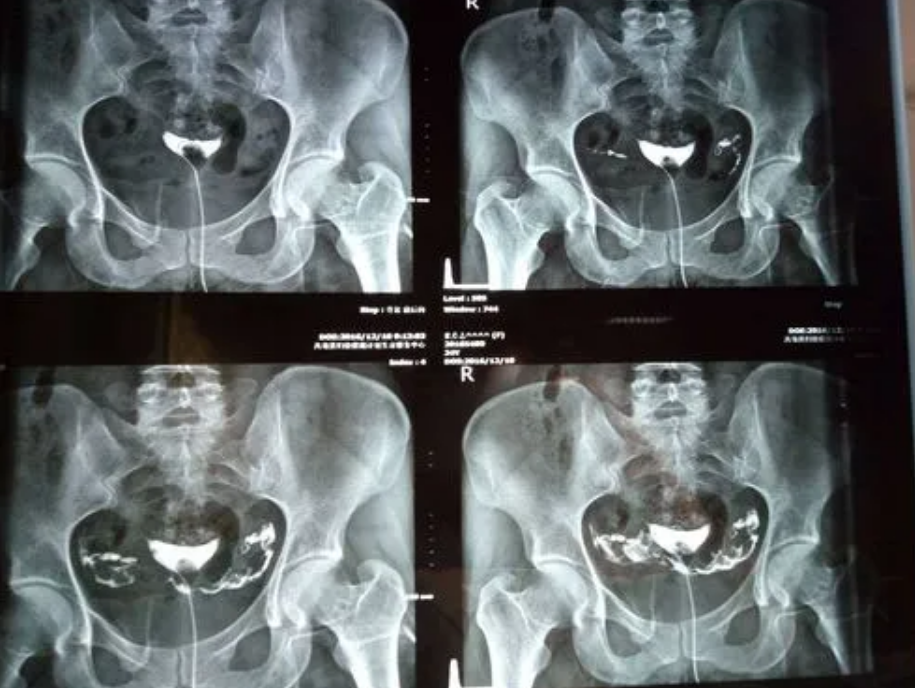

输卵管造影经X线的子宫输卵管造影是通过导管向宫腔及输卵管注入造影剂,利用X线诊断仪行X 线透视及摄片,根据造影剂在输卵管及盆腔内的显影情况来了解输卵管是否通畅、阻塞部位及宫腔形态的一种检查方法。很多对于手术紧张的女性想要知道该手术的过程是什么?今天我们就为大家带来这方面的内容,希望可以帮到大家!输卵管造影手术过程1.造影时患者仰卧于X光机操作平台上。常规消毒外阴及阴道,铺无菌巾,再次检查子宫位置及

输卵管造影经X线的子宫输卵管造影是通过导管向宫腔及输卵管注入造影剂,利用X线诊断仪行X 线透视及摄片,根据造影剂在输卵管及盆腔内的显影情况来了解输卵管是否通畅、阻塞部位及宫腔形态的一种检查方法。很多对于手术紧张的女性想要知道该手术的过程是什么?今天我们就为大家带来这方面的内容,希望可以帮到大家!输卵管造影手术过程1、造影时患者仰卧于X光机操作平台上。常规消毒外阴及阴道,铺无菌巾,再次检查子宫位置及